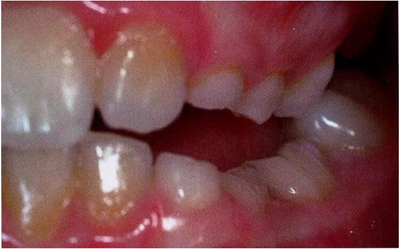

圖8展示了一張5歲孩子右下第二乳磨牙嚴重下沉的口內(nèi)像。臨床檢查可見右下第一乳磨牙遠中傾斜,朝向下沉乳牙。X線片檢查顯示所有恒牙胚都存在(圖9)。無論是臨床還是影像學,都可檢查到有齲齒的存在。鑒于這顆下沉乳牙在年齡較小時就已經(jīng)非常嚴重,同時還患有齲病,因此決定予以拔除。后期在放置間隙保持器的同時還應持續(xù)觀察監(jiān)測右下第一恒磨牙和第二前磨牙的萌出情況。

文獻直達|乳磨牙下沉的臨床管理

圖8:一名五歲患兒右側(cè)下頜第二乳磨牙嚴重下沉臨床像

圖9:一名五歲患兒右側(cè)下頜第二乳磨牙嚴重下沉的曲面體層片